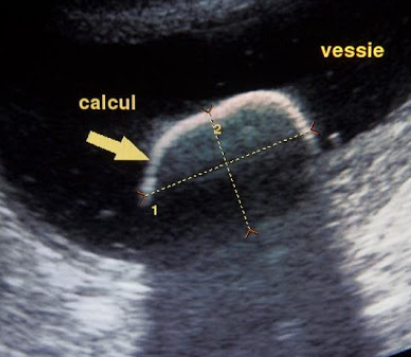

Nous réalisons aussi et surtout des échographies thoraciques et abdominales. Ces échographies sont pour nous l’occasion d’observer de nombreux organes comme les poumons, le foie, les reins, la rate, le pancréas, le tube digestif, la vessie, les glandes surrénales, la prostate, les ovaires, l’utérus, la prostate. Les anomalies observées peuvent nous orienter vers un dysfonctionnement organique bien spécifique. Ces échographies nous permettent également de réaliser des ponctions écho-guidées des anomalies observées (ponction dans les organes internes en se guidant grâce à l’échographe) et pouvoir ainsi transmettre ces prélèvements à des laboratoires d’analyses cytologiques ou histologiques par exemple. Nous pouvons dans un contexte plus positif suivre le bon déroulement d’une gestation en observant les mouvements cardiaques des fœtus.

En toute transparence, un compte-rendu complet et imagé de l’examen vous sera transmis par mail ou par papier.